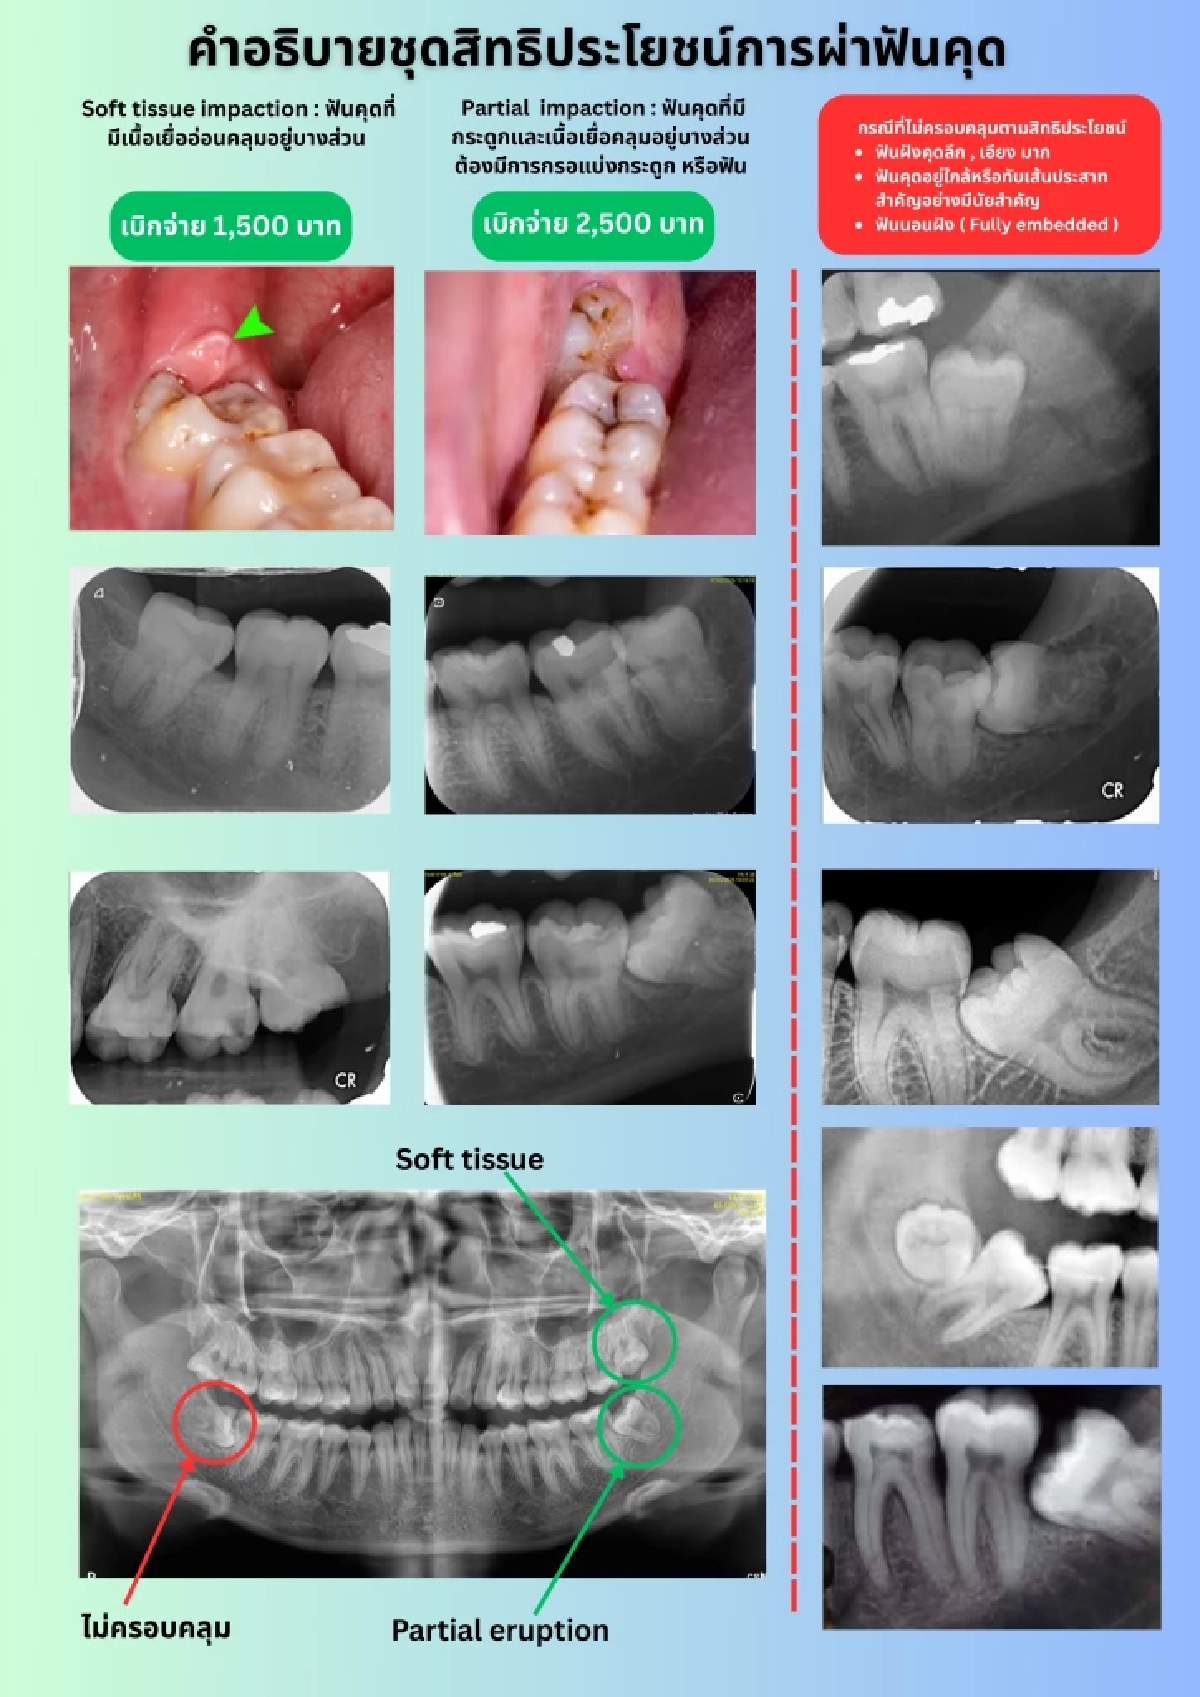

สำหรับฟันคุดที่อยู่ในกระดูกบางส่วน (Partial Bony Impaction Tooth) ที่ทันตแพทยสภาเสนอต่อสำนักงานประกันสังคม จะเป็นกรณีเฉพาะที่ไม่ซับซ้อน มีระดับความยากที่เหมาะสมกับการให้บริการของคลินิกทันตกรรมเอกชนโดยทั่วไป ซึ่งทันตแพทยสภาได้เคยให้ข้อเสนอแนะต่อสำนักงานประกันสังคม ว่าควรมีภาพฟันคุดประกาศอย่างเป็นทางการ เพื่ออธิบายว่าลักษณะฟันคุดและภาพถ่ายรังสีฟันคุดแบบใด ที่ครอบคลุมสิทธิประโยชน์ และแบบใดที่อยู่นอกเหนือสิทธิประโยชน์ เพื่อให้เกิดความเข้าใจกันในการสื่อสารระหว่างสถานพยาบาลและผู้ประกันตน

สำหรับสิทธิประโยชน์ผ่าฟันคุดของประกันสังคม จะครอบคลุมเฉพาะ ฟันคุดที่ขึ้นไม่ได้เนื่องจากมีเนื้อเยื่ออ่อนคลุมอยู่บางส่วน (Soft Tissue Impaction Tooth) และฟันคุดที่อยู่ในกระดูกบางส่วน (Partial Bony Impaction Tooth) เท่านั้น ฟันคุดที่มีกระดูกคลุมอยู่ทั้งซี่ (Completed Bony Impaction Tooth) จะไม่อยู่ในสิทธิประโยชน์ที่ประกันสังคมกำหนดไว้